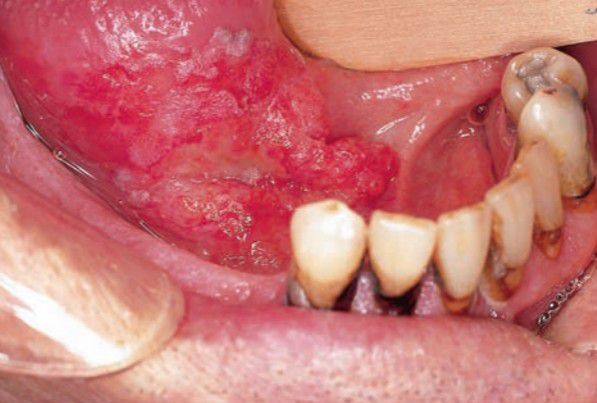

Squamous cell carcinoma of oral cavity

Indurated, nonpainful ulcer with rolled margins; most commonly found on lateral tongue and floor of mouth; males affected twice as often as females.